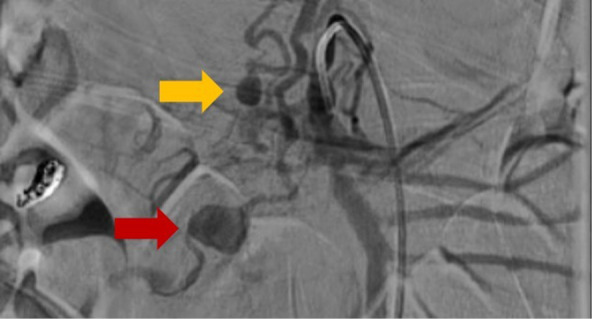

Unveiling the unexpected: spontaneous ruptured pancreaticoduodenal artery pseudoaneurysm with retroperitoneal hematoma requiring pancreaticoduodenectomy.